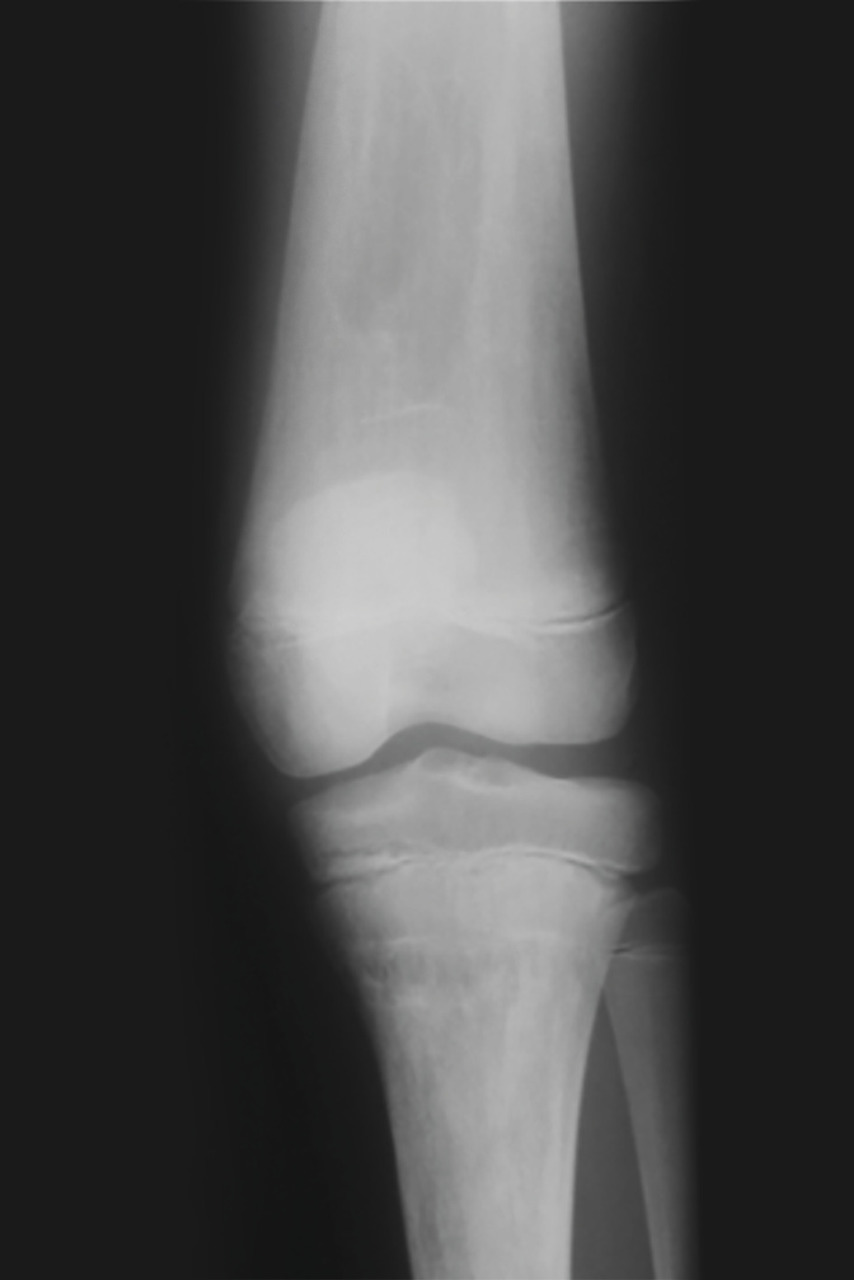

Les infarctus osseux peuvent se manifester par une fièvre modérée associée à un érythème et un œdème, localisés le plus souvent en regard des métaphyses et diaphyses des os longs. L’ostéonécrose aseptique, qui résulte de phénomènes identiques, est localisée aux épiphyses et atteint de manière préférentielle les têtes fémorales, les têtes humérales, et plus rarement les condyles fémoraux, les plateaux tibiaux, ou les corps vertébraux (vertebra plana). Les ostéonécroses épiphysaires peuvent conduire à une arthrose, justifiant à terme la pose d’une prothèse. La déformation des fémurs en flacon d’Erlenmeyer (fig. 3 ) correspond à un élargissement métaphysodiaphysaire des os longs, par défaut de remodelage osseux et de tubulation métaphysaire. Enfin, il existe une réduction de la densité minérale osseuse, avec un risque d’ostéoporose.

Les infarctus osseux peuvent se manifester par une fièvre modérée associée à un érythème et un œdème, localisés le plus souvent en regard des métaphyses et diaphyses des os longs. L’ostéonécrose aseptique, qui résulte de phénomènes identiques, est localisée aux épiphyses et atteint de manière préférentielle les têtes fémorales, les têtes humérales, et plus rarement les condyles fémoraux, les plateaux tibiaux, ou les corps vertébraux (vertebra plana). Les ostéonécroses épiphysaires peuvent conduire à une arthrose, justifiant à terme la pose d’une prothèse. La déformation des fémurs en flacon d’Erlenmeyer (

En ce qui concerne les imageries, l’échographie abdominale reste largement utilisée en première intention, car facilement disponible. Néanmoins, l’imagerie par résonance magnétique (IRM) abdominale est l’examen de choix pour évaluer les dimensions de la rate et du foie, ainsi que leur morphologie, et pour évaluer les nodules en rapport avec des « gaucheromes ». L’IRM est également l’examen de choix pour évaluer l’atteinte osseuse, pour quantifier l’infiltration osseuse par les cellules de Gaucher, l’extension des lésions, leur caractère aigu ou ancien, et pour le suivi des patients. Les radiographies osseuses sont utiles pour toute localisation symptomatique et le suivi des ostéonécroses. Les lésions rencontrées sont multiples : déformation fémorale en flacon d’Erlenmeyer (fig. 3 ), lésions lytiques, amincissement de la corticale, lésions d’ostéo-condensation, fractures. Enfin, l’ostéodensitométrie permet de détecter une ostéopénie ou une ostéoporose, fréquentes dans la maladie de Gaucher.

En ce qui concerne les imageries, l’échographie abdominale reste largement utilisée en première intention, car facilement disponible. Néanmoins, l’imagerie par résonance magnétique (IRM) abdominale est l’examen de choix pour évaluer les dimensions de la rate et du foie, ainsi que leur morphologie, et pour évaluer les nodules en rapport avec des « gaucheromes ». L’IRM est également l’examen de choix pour évaluer l’atteinte osseuse, pour quantifier l’infiltration osseuse par les cellules de Gaucher, l’extension des lésions, leur caractère aigu ou ancien, et pour le suivi des patients. Les radiographies osseuses sont utiles pour toute localisation symptomatique et le suivi des ostéonécroses. Les lésions rencontrées sont multiples : déformation fémorale en flacon d’Erlenmeyer (